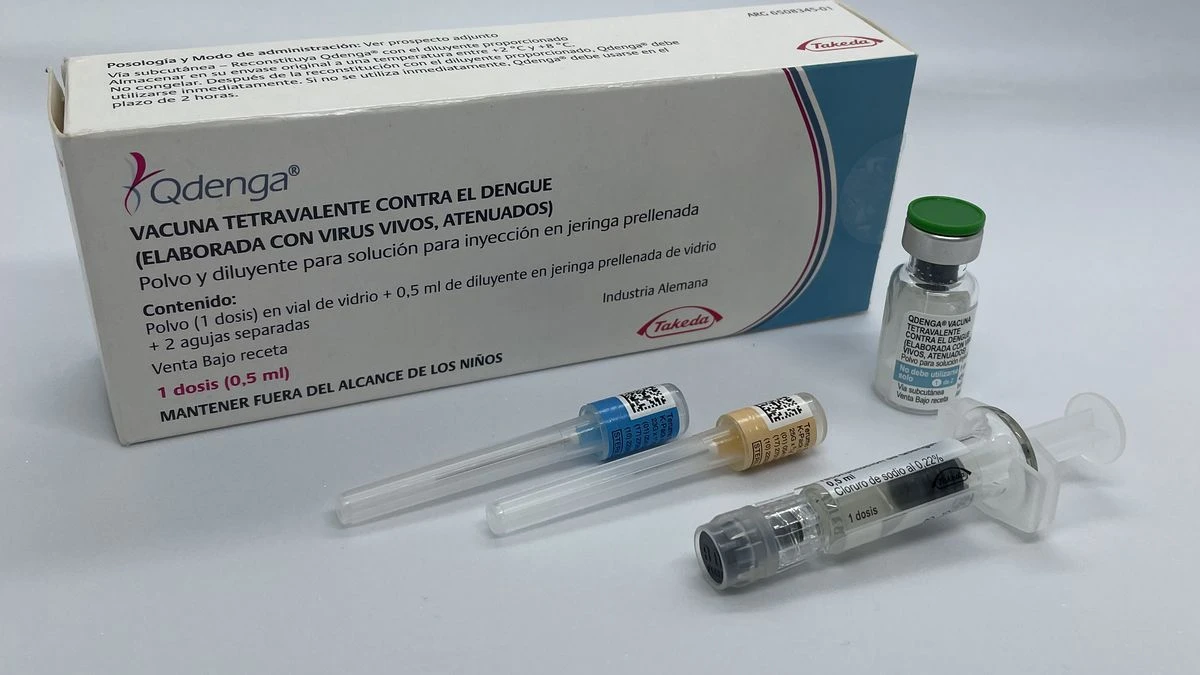

El debate por la vacunación contra el dengue

“La Comisión Nacional de Inmunología recomendó la vacunación en las poblaciones de riesgo y en los lugares en donde hay mayor circulación”, apunta Nelson Castro. “Esta discusión que se da en Argentina me parece increíble, más cuando el ministro de Salud (Mario Russo) dice que hay una presión de los medios y los laboratorios para instalar el tema. Me da mucha pena. Repito, no aprendemos nada de lo que pasó”, destaca el periodista de Radio Rivadavia y eltrece.

“El Gobierno sostiene que la Organización Panamericana de la Salud no la recomienda, pero la Agencia Médico Europea, sí. Eso es lo importante. Brasil está llevando adelante un estudio muy interesante, y el 31 de enero salió un paper en The New England Journal of Medicine en el que se menciona que un estudio patrocinado por un laboratorio y el Ministerio de Salud brasileño llegó a la conclusión de que se les recomienda la vacuna a menores de 6 a 16 años y adultos, especialmente quienes tuvieron la enfermedad. De esto se trata. Son datos concretos que los médicos seguimos a diario”, apunta Nelson.

Más allá de ello, Castro advierte que tomar la decisión de vacunarse tiene que estar basada en la recomendación estrictamente personal que un médico infectólogo haga en cada caso: “Por lo que noto, los pacientes reciben la recomendación de un profesional de la salud de vacunarse un tiempo después de haber sufrido dengue. En los casos de Misiones y Corrientes, por ejemplo, decidieron aplicar la vacuna de forma gratuita por la situación que se viene viviendo”, completa